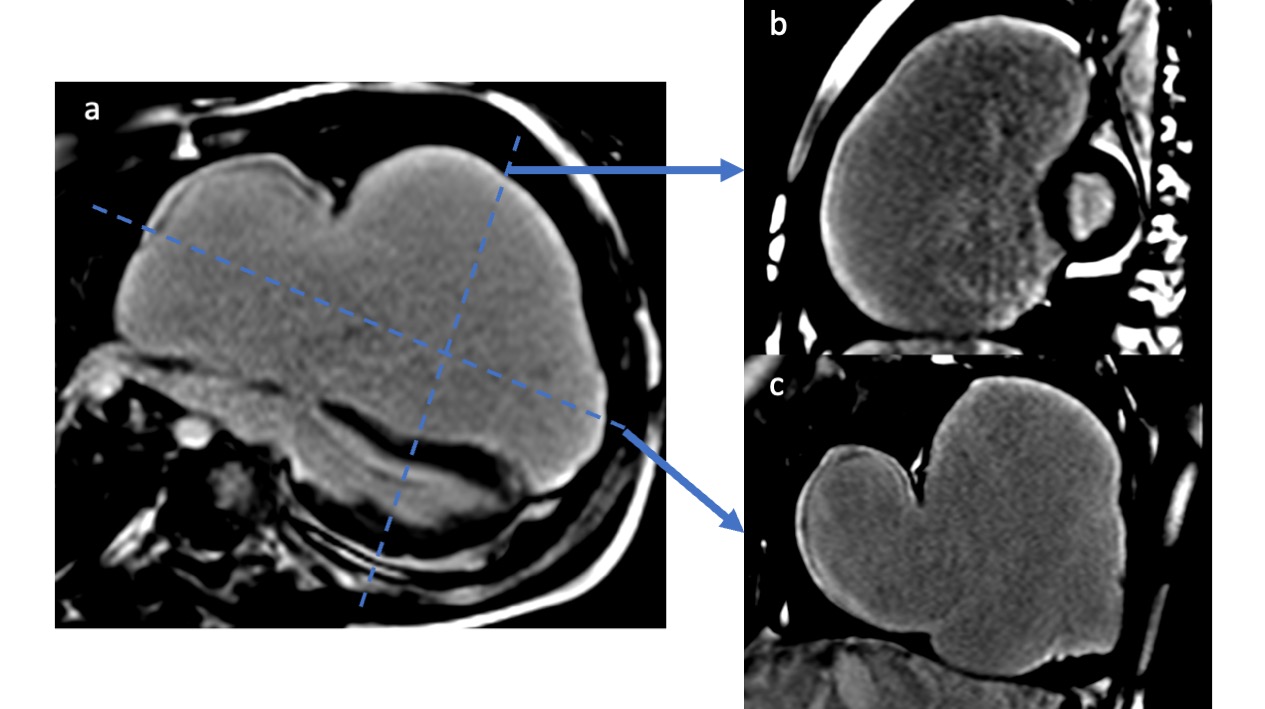

Figure 2. Cine bSSFP images across different cardiac phases in four-chamber (top row) and short-axis (bottom row) views demonstrate a marked diastolic leftward shift of the interventricular septum (arrowheads in the four-chamber view and arrows in the short-axis view), resulting in the characteristic left ventricular “D-shape” and indicating abnormal ventricular interdependence.